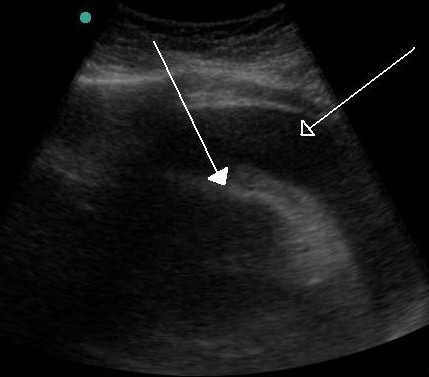

Pericardial effusion is the acute or chronic accumulation of fluid in the pericardial space (between the parietal and the visceral pericardium) and is often associated with a variety.